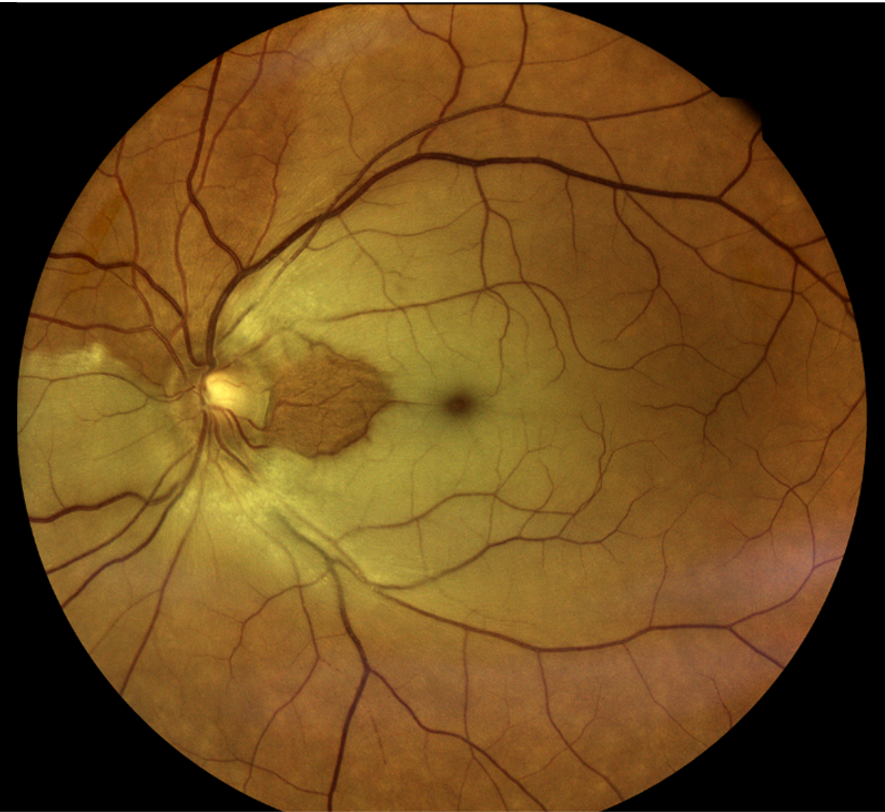

Rétinophotos couleurs d’un patient atteint d’OACR de l’œil gauche avec une « macula rouge cerise »

Appelé aussi « l’AVC de l’œil », l’OAR  est une urgence ophtalmologique. Elle survient quand l’artère centrale de la rétine se bouche brutalement, privant ainsi l’oxygénation de la rétine.

Il existe des formes complètes, lorsque l’artère centrale s’obstrue (OACR) et des formes partielles lorsqu’une branche artérielle qui est touchée (OBAR). L’atteinte de l’œil est plus importante lorsqu’il s’agit d’une OACR, et peut aller jusqu’à la cécité.